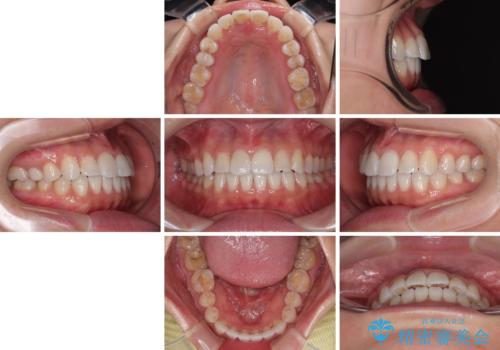

捻れた前歯を楽して改善 ワイヤー装置での非抜歯矯正

ご本人の中では2年近くかかるものと思っていたそうですが、1年で治療を終えることができ、大変満足していらっしゃいました。

- 上下前歯のデコボコを気にして来院された患者様です。

ワイヤー矯正でもマウスピース矯正でも可能でしたが、短期間で、自身の手を煩わせることなく治療を行いたいとのことで、ワイヤー装置にて矯正治療を行うこととしました。